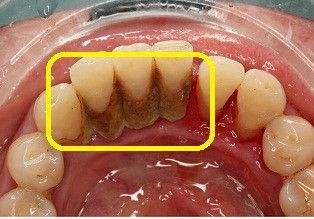

遭牙结石侵蚀的牙根

牙结石会在牙齿内侧不断积累成型的,会给患者的生活带来不少的负面影响:

2,引发口腔内部疾病。因为牙结石在牙齿上不断沉积,且与牙龈相连,长期刺激着牙周组织,很容易引发牙龈肿痛、牙周炎等疾病的发生。

3,可能会导致牙齿脱落的。牙结石在口腔中会不断积累且不断侵入龈下,也会不断滋生细菌,侵入到牙根位置,就会使牙齿从根部变得松动,也会加大牙齿脱落的风险。